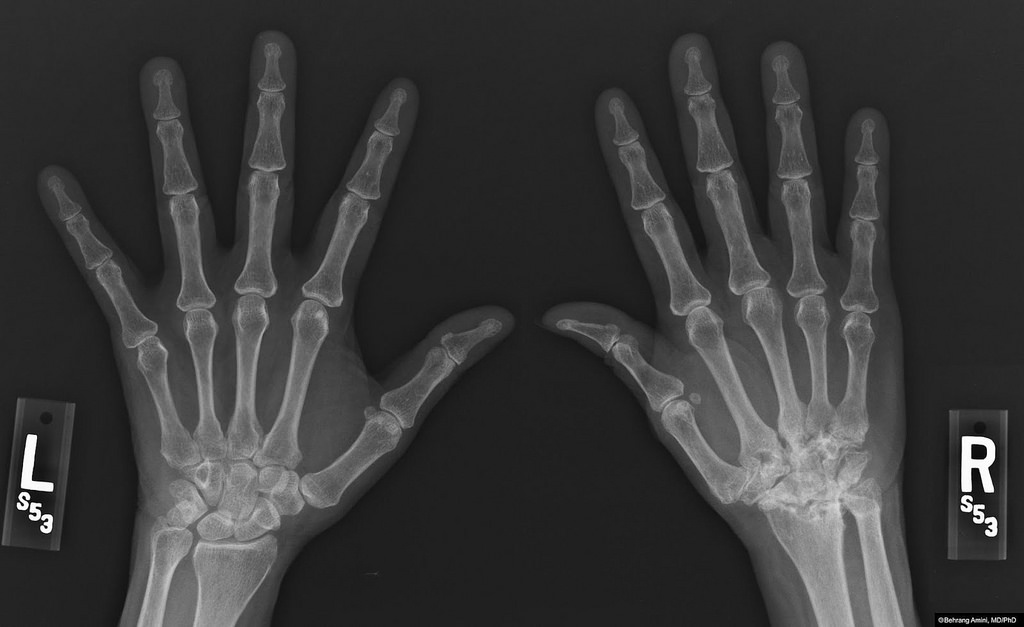

Arthritis and the Benefits of Prolotherapy

Arthritis is one of the reasons why the joints may be sore. It occurs when:

In arthritis, the cartilages, ligaments, and bones may degenerate causing joint instability, malfunction, and pain. When any of these parts are damaged, certain mechanical, structural, and physiologic changes happen, and joint stability and flexibility becomes compromised.